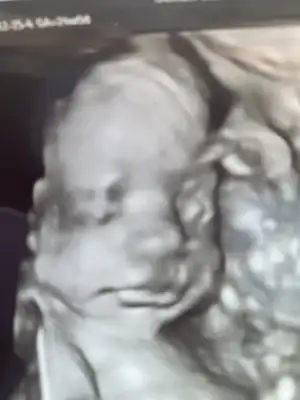

Biz kontrolden geldik doktor detaylı yeterli dedi sonuçlar güzel bende kontrol ederim şimdi dedi pazartesi olan randevu iptal

Minnoşumu gördüm yine ayy keşke hergün böyle görebilsem 🙏

İlk kez yüzünü bu kadar net gördük ❤️🧿

1 hafta önde ama değişir takılma dedi 28 cm 532 gram ölçtü ❤️ Vitaminler aynen devam osteocare ikiye çıkardı mide yanmamı sormayı unuttum heyecandan 🙈 rabbim hepimize sağ Salim kucağımıza almayı nasip etsin 🙏

ne kadar net çıkmış 🚀 al sana ilk vesikalık foto😍

Minnos kız mı 🤩öyle bı naiflik var görüntüde.

Bugün keyfi yerindeydi minnoşumun💕

Eşime dedim net görünürse video al diye ama biz hala o kadar heyecanlıyız ki ağzımız açık izlemekten hiç bişey yapamıyoruz bende doktorla konuşuyor oluyorum genelde videomuz ilk zamanların var son zamanlarda yok maalesef 😅

Üç hafta sonra şeker testi için çağırdı çabucak geçer inşallah 🙏